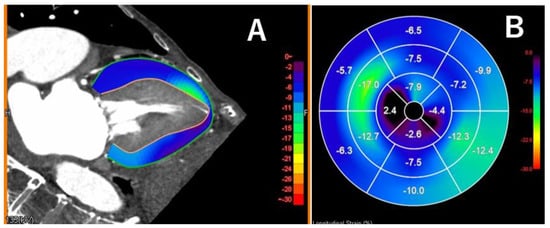

3.6. Myocardial Strain Analysis on Computed Tomography

- Bernhard, B.; Schütze, J.; Leib, Z.L.; Spano, G.; Berto, M.B.; Bakula, A.; Tomii, D.; Shiri, I.; Brugger, N.; De Marchi, S.; et al. Myocardial analysis from routine 4D cardiac-CT to predict reverse remodeling and clinical outcomes after transcatheter aortic valve implantation. Eur. J. Radiol. 2024, 175, 111425. [Google Scholar] [CrossRef]